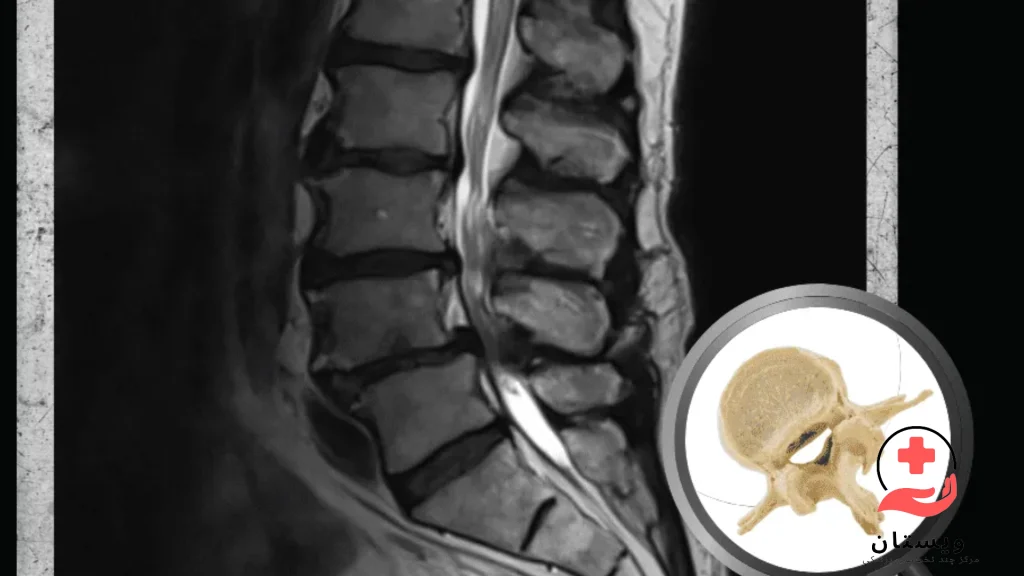

ام آر آی کمر یکی از دقیقترین روشهای تصویربرداری پزشکی برای بررسی ساختارهای داخلی ناحیه کمری ستون فقرات است. در این روش، بدون استفاده از اشعه، با کمک میدان مغناطیسی و امواج رادیویی، تصاویر واضحی از مهرهها، دیسکها، نخاع، اعصاب و بافتهای اطراف کمر گرفته میشود.

ام آر آی کمر و لگن یکی از دقیقترین و مطمئنترین روشهای تصویربرداری پزشکی است که برای بررسی علت درد، محدودیت حرکت، یا مشکلات عصبی در ناحیه پایینتنه به کار میرود. در روش ام آر آی کمر و لگن با استفاده از میدان مغناطیسی قوی و امواج رادیویی، تصاویر بسیار واضحی از مهرههای کمری، دیسکها، مفاصل لگن، عضلات، اعصاب و بافتهای نرم اطراف آن تهیه میشود—همه اینها بدون استفاده از اشعه ایکس و بهصورت کاملاً غیرتهاجمی.

پزشکان از ام آر آی کمر و لگن برای تشخیص بیماریهایی مانند فتق دیسک، آرتروز مفصل لگن، تنگی کانال نخاعی، التهاب اعصاب سیاتیک، تومورها یا عفونتهای پنهان استفاده میکنند. همچنین، اگر بیمار دچار درد مزمن پایینکمر یا باسن باشد که به درمانهای معمول پاسخ نمیدهد، انجام ام آر آی کمر و لگن ضروری است.